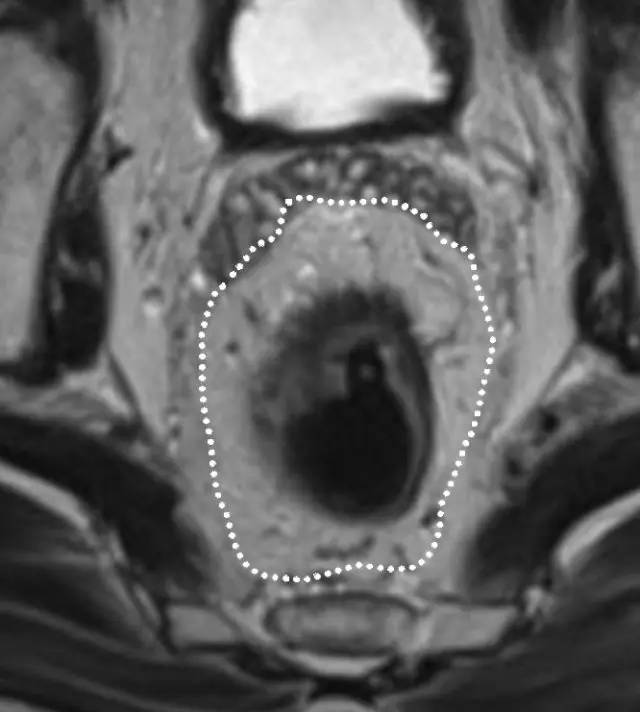

图 5 远端直肠半圆形 T2 肿瘤,与外部肌层分界明显

MR 无法区分肿瘤是局限于黏膜下层还是浸润至固有肌层,直肠内超声(US)能够更准确地区分 T1 和 T2。T1~2 期肿瘤未穿透肠壁,预后较好,T1~2 期 MRI 上可见直肠肠壁完整的黑色边界。

T3 分期

MRI 检测直肠周围组织浸润的敏感性为 82%,肿瘤侵犯或结缔组织增生反应均可表现为直肠周围浸润,为了避免分期不足,出现直肠周围浸润即作为 T3 期肿瘤。